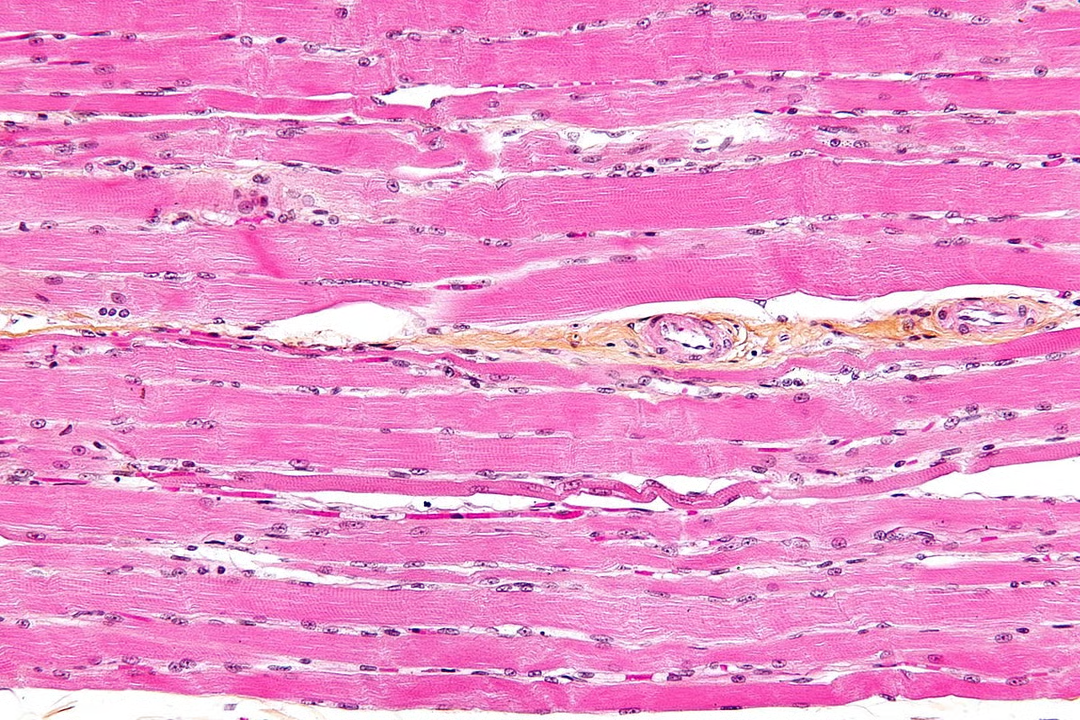

striated muscle

makes up muscles in body attached to skeleton (striated=striped/streaky) made of muscle fibres

3 muscle fibre features that make it a highly specialised cell like unit

each contains an organised arragnement of contractile proteins in cytoplasm

each surrounded by csm

each contains many nuclei which is why nto usually referred to as cedlls

diff parts of muscle fibres w diff names to equivalent parts

csm = sarcolemma

cyto = sarcoplasm

what does sarcoplasm contain and why

mitoch for carrying out aerobic resp to generate atp required for muscle contraction

myofibrils (bundles of actin and myosin filaments) which slide past each other during muscle contraction